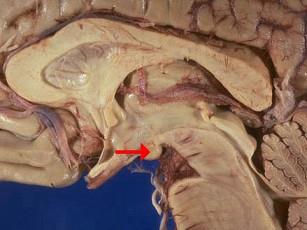

如图箭头所示为大脑哪个部位 ( )A、乳头体B、垂体C、后连合D、室间孔E、前连合

问题 如图箭头所示为大脑哪个部位 ( )

选项 A、乳头体 B、垂体 C、后连合 D、室间孔 E、前连合

答案 A